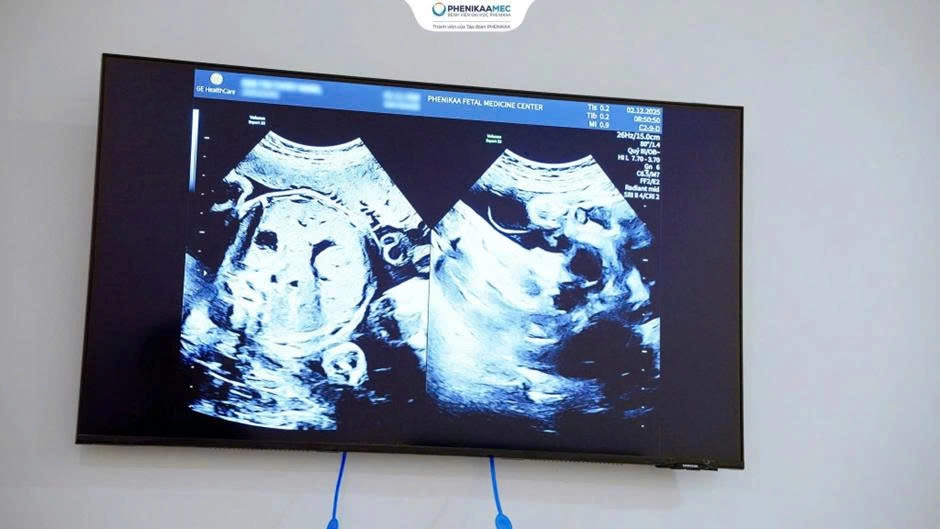

Sản phụ T.H (37 tuổi) mang thai nhờ phương pháp hỗ trợ sinh sản IUI sau 10 năm hiếm muộn. Kết quả siêu âm sớm cho thấy song thai hai bánh rau – hai buồng ối cùng với tiền sử hiếm muộn đã được TS. BS Nguyễn Thị Sim - Giám đốc Trung tâm Y học Bào thai PhenikaaMec nhận diện đây là thai kỳ nguy cơ cao và theo dõi đặc biệt ngay từ giai đoạn sớm của thai kỳ.

Tiếp nhận ca bệnh, TS. BS Nguyễn Thị Sim đã áp dụng quy trình siêu âm theo tiêu chuẩn ISOUG (International Society of Ultrasound in Obstetrics and Gynecology). Mỗi thai nhi được đánh giá tăng trưởng độc lập, theo dõi chặt chẽ Doppler bánh rau và tuần hoàn thai, từ đó phát hiện sớm những dấu hiệu suy thai tiềm ẩn. Trên cơ sở đó, sản phụ được tư vấn cá thể hóa về chế độ dinh dưỡng, sinh hoạt và kiểm soát đường huyết, nhằm tạo nền tảng ổn định cho hành trình giữ thai kéo dài.